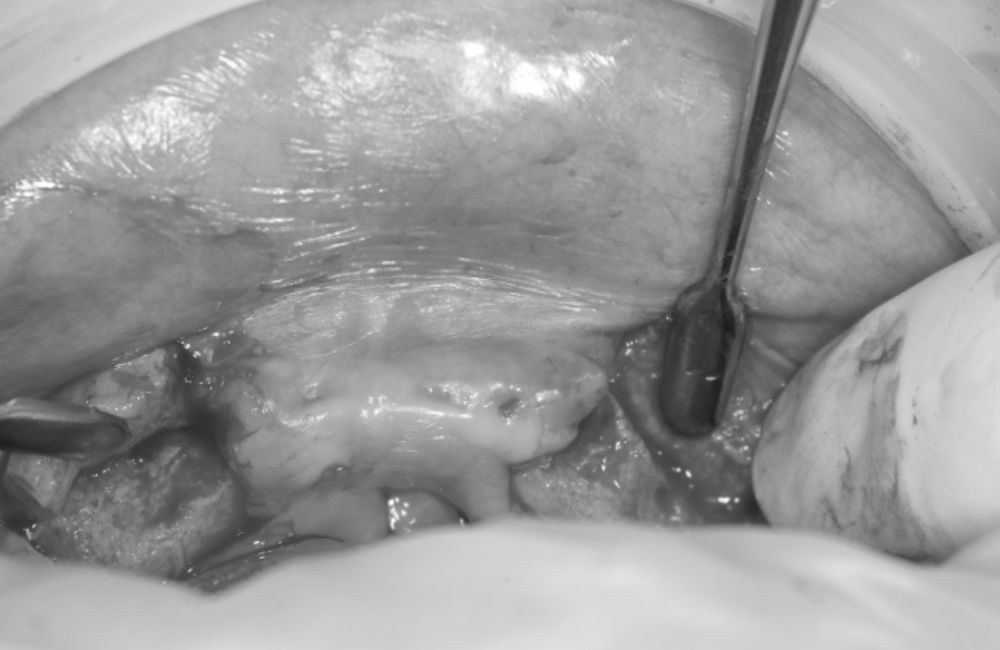

鎮静下でのインプラントオペ

鎮静下でのインプラントオペです。

実際は全工程で1時間半くらいかかりましたが、患者様にとってみては、痛みがなく、寝たような状態なのであっという間という感じでしょうか。

患者様はたいへん怖がりな方でしたので、インプラントの一次手術(インプラントの埋入オペ)だけでなく、二次オペ(インプラントの頭出しのオペ)も鎮静下で行いました。

合計2回静脈内鎮静を行いました。